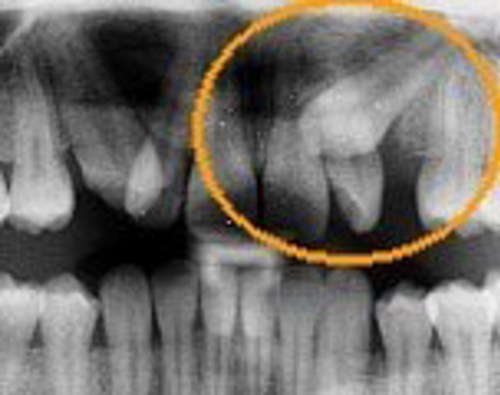

Det kan blive nødvendigt, at operere tanden frem og derefter sætte bøjle på, hvis den ikke kommer rigtigt frem i kæben.

Nedenfor ses en billedserie, der illustrere forløbet.

- Røntgenbillede af hjørnetand, som ikke kan komme frem.